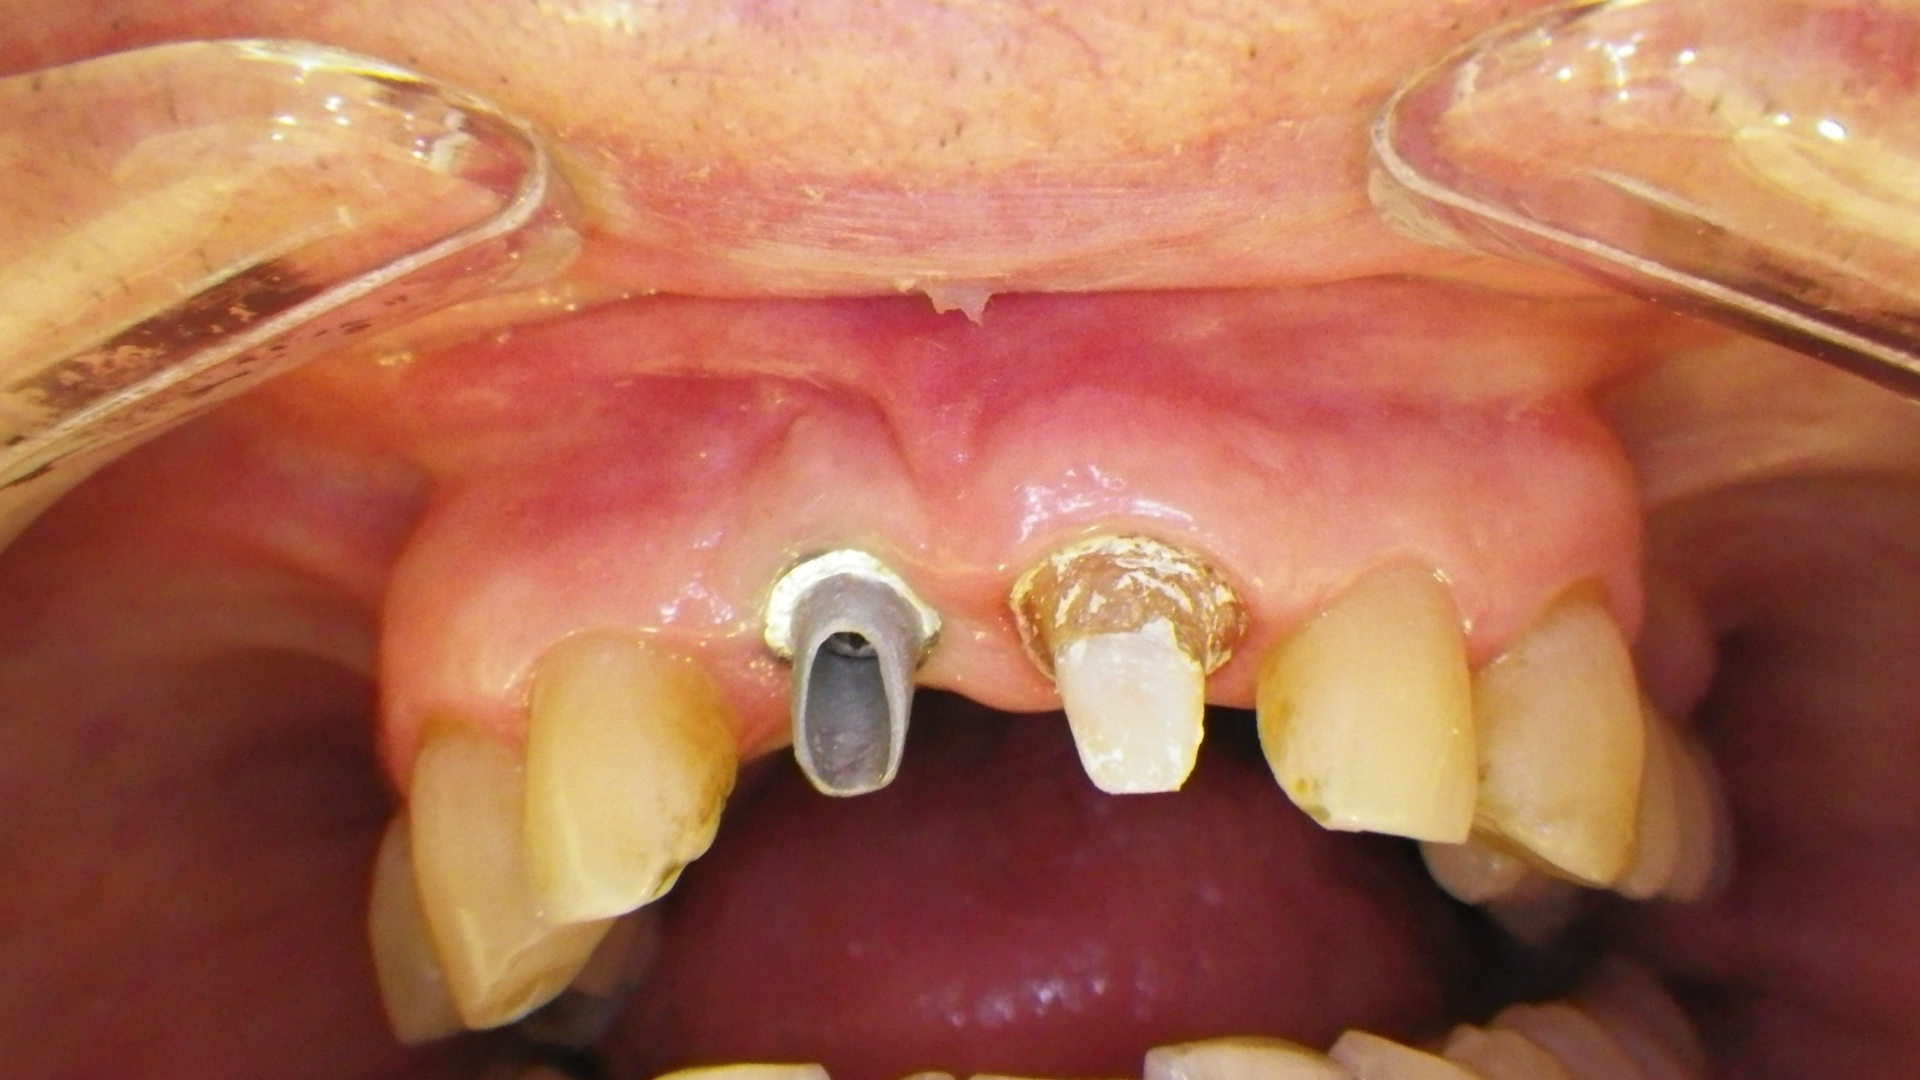

Reemplazo de corona

En este caso se trata de una paciente que recibió un bochazo de Hockey en la adolescencia y tuvo una prótesis fija durante más de 20 años.